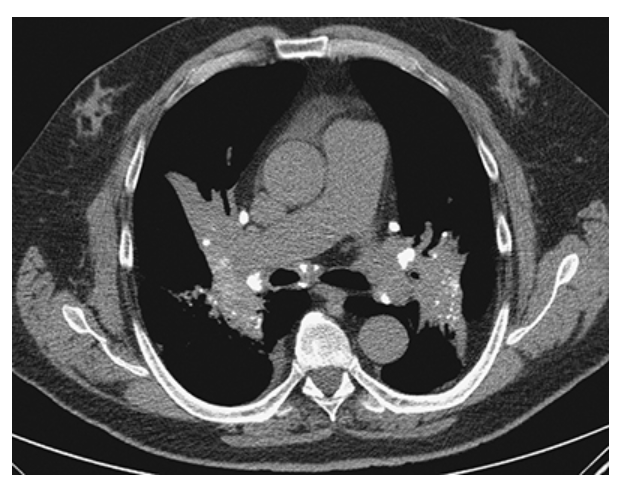

Hodgkin Disease. Axial CECT of the chest shows bulky anterior mediastinal and left axillary lymphadenopathy in this patient with Hodgkin lymphoma.

Hodgkin Disease. Axial CECT of the chest shows the congolomeration of nodes extending down and appearing as an anterior mediastinal mass.